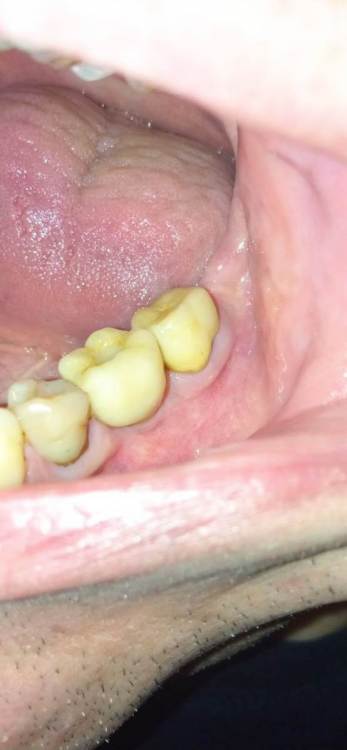

Jonik Опубликовано 29 июня, 2022 Поделиться Опубликовано 29 июня, 2022 Здравствуйте! Поставили коронку на временный цемент, недавно она отвалилась, нужно идти фиксировать на постоянный цемент но коронка мне не совсем нравится. Слой керамики в некоторых местах выходит за пределы металлического основания. Где то слой керамики заглажен к металлу, а где то имеет утолщение. Можно ли фиксировать такую коронку или переделывать. Если поставить эту коронку, могут ли потом возникнуть проблемы с гигиеной или с десной? Ссылка на комментарий

Jonik Опубликовано 30 июня, 2022 Автор Поделиться Опубликовано 30 июня, 2022 31 минуту назад, Doc сказал: Тут весь вопрос в том, что это было. Если керамическое плечо, то это нормально и даже когда-то приветствовалось. Если же техник просто металл не дотянул, а потом решил керамикой доляпать, то это совсем другой вопрос. Как во рту сидит? По десне все хорошо, либо над, либо глубоко под? Где уступ? Коронка точно без плеча. Когда была первая примерка врач отправил коронку на корректировку, сказал что нужно поправить немного. Может как раз это и был недотянутый метал. Как во рту сидит мне не нравится, местами под десну заходит. Ближе к уступу коронка кажется массивной, имеет утолщение возле десны, как бы наплывает на десну, приходится промывать ирригатором. Ссылка на комментарий